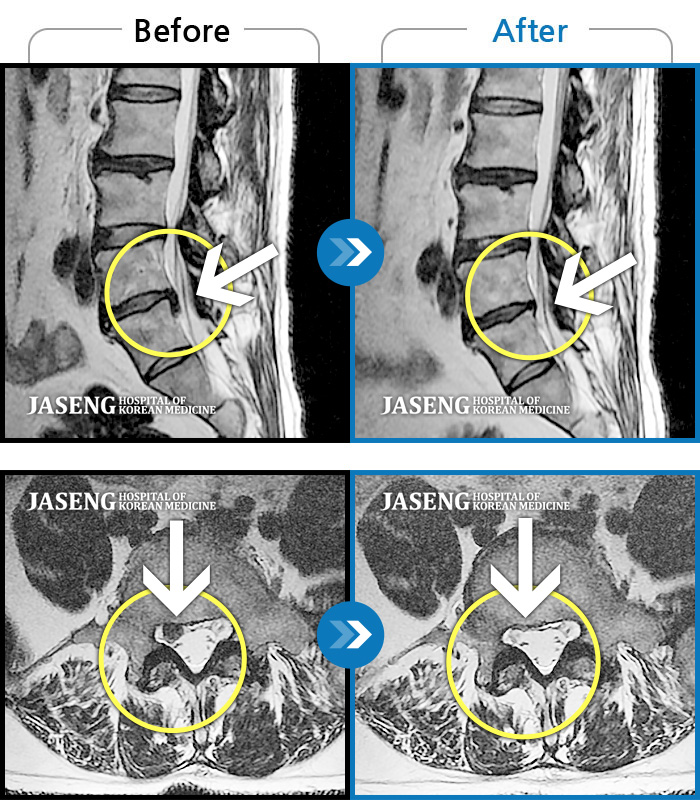

MRI 치료사례

허리디스크로 우측 발목까지 방사통